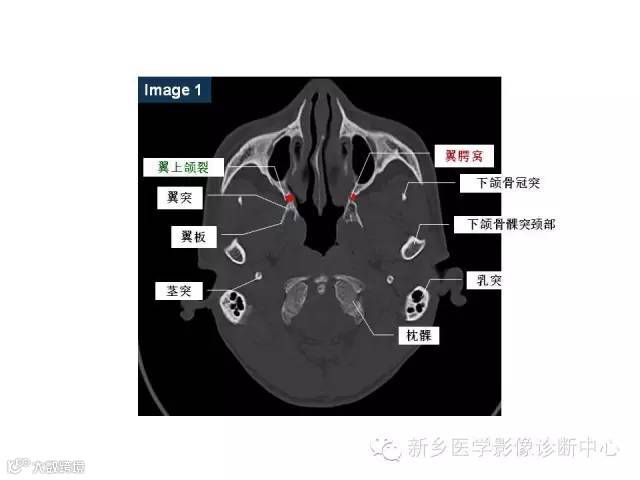

颅底孔道解剖详解

值得收藏!